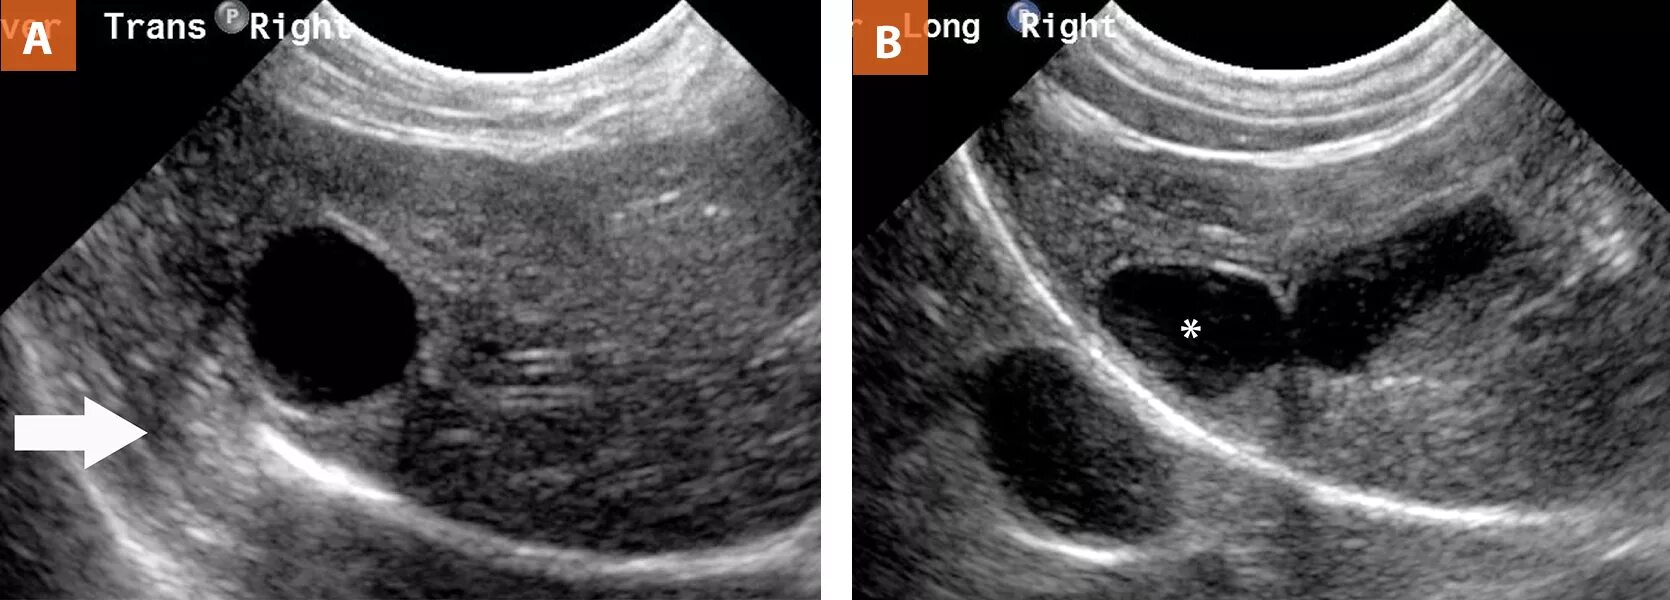

Анэхогенное содержимое желчного что это